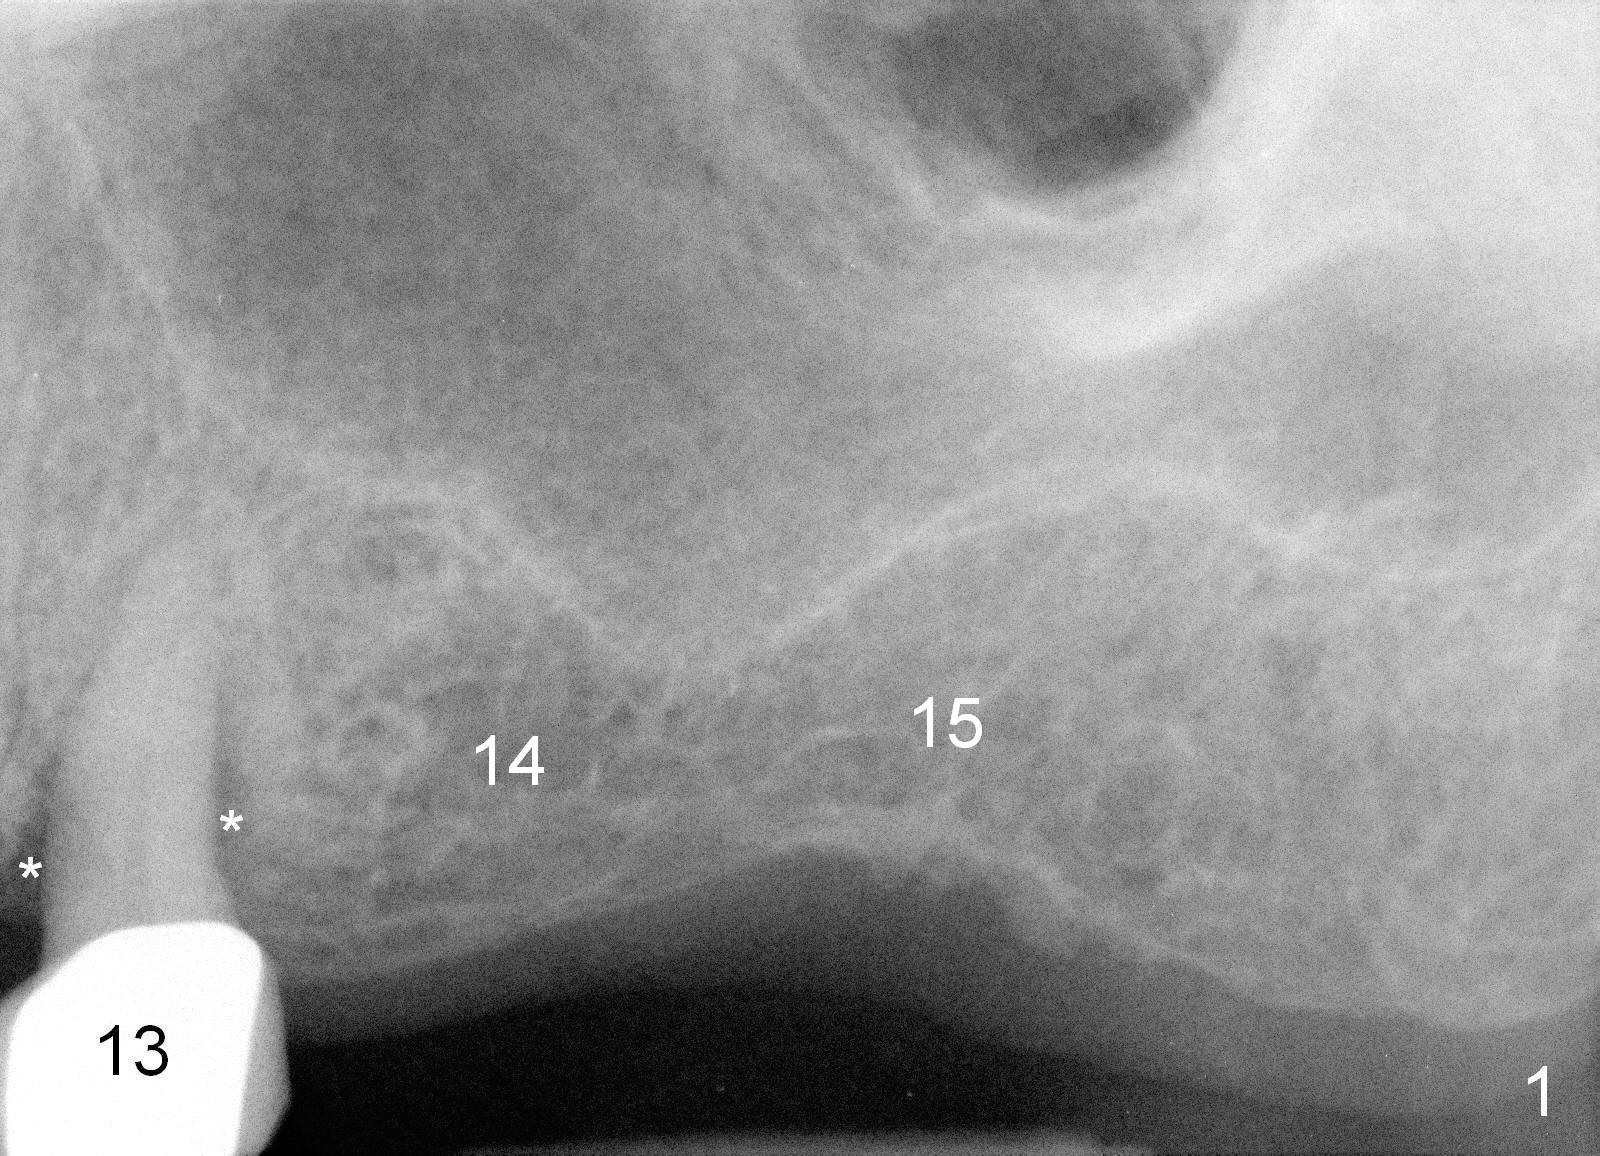

Mrs. Goh (71 years old) has lost 4 upper molars (Fig.1,6). The 1st sign of overload is increased periodontal space around the tooth #13 (Fig.1 *). The best way to tackle the overload is to place 4 implants. The 1st step is for the site of #14 (Fig.2: design; Fig.3: 4.5x11 mm tap; Fig.4: 5x11 mm implant). The 2nd sign of overload is repeated dislodgement of the implant supported crown. The 3rd sign of overload is bone loss around the implant 6 months post cementation (Fig.5 *). The 4th sign of overload is subgingival crown fracture of the tooth #5 (Fig.6).